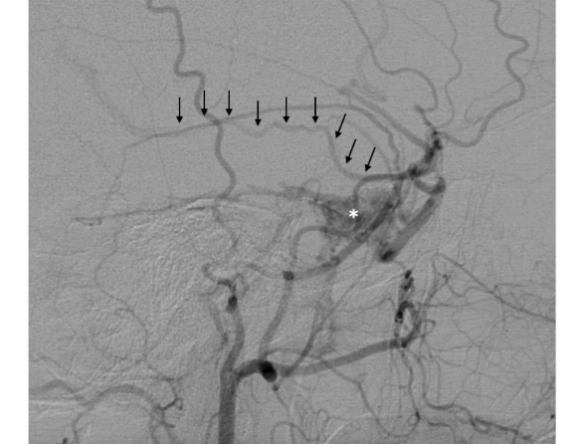

Indeed, diagnostic angiography showed a DAVF of the right cavernous sinus, fed by branches of the right external carotid artery, with drainage to the ipsilateral cavernous sinus and backflow into the superficial middle cerebral vein (Figure 1). Treatment was indicated because of the retrograde flow into the middle cerebral vein, which poses a risk of cerebral haemorrhage. Two weeks after diagnostic angiography, the patient was admitted for treatment. A repeat angiogram showed a change in the fistula pattern, with anterior venous drainage to the superior ophthalmic vein and facial vein. The decision was made to catheterize the fistula via this route and attempt coil and Histoacryl® embolization. Two micro catheters were navigated until de "foot" of the vein, one Magic 1.2 (Balt Extrusion, Montmorency, France), for the glue injection and and one excelsior SL 10 (Stryker Neurovascular, Fremont, California, USA), for coils deployment. First the coils were placed to reduce the flow inside the ophthalmic vein, and after glue was injected. Control angiography showed only partial occlusion of the fistula. The fistula was again catheterized selectively, via the middle meningeal artery, with a sonic microcatheter (Balt Extrusion, Montmorency, France) and an injection of Onyx® liquid embolic system was administered, with complete obliteration of the fistula (Figure 2). Postoperatively, the patient reported right-sided eye pain and slight proptosis. Dexamethasone 4 mg q6h was prescribed, and symptoms had resolved completely by the fourth postoperative day. The patient was asymptomatic on discharge. At 3-month follow-up, she remained free of symptoms and no longer required analgesia.

Figure 1: Selective angiography of the right external carotid artery, in the lateral view, showing a fistula (asterisk) with retrograde drainage into the superficial middle cerebral vein (arrows).